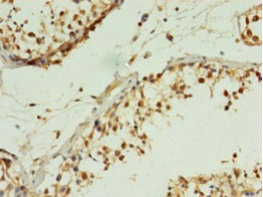

Immunohistochemistry of paraffin-embedded human testis tissue using CSB-PA875639LA01HU at dilution of 1:100